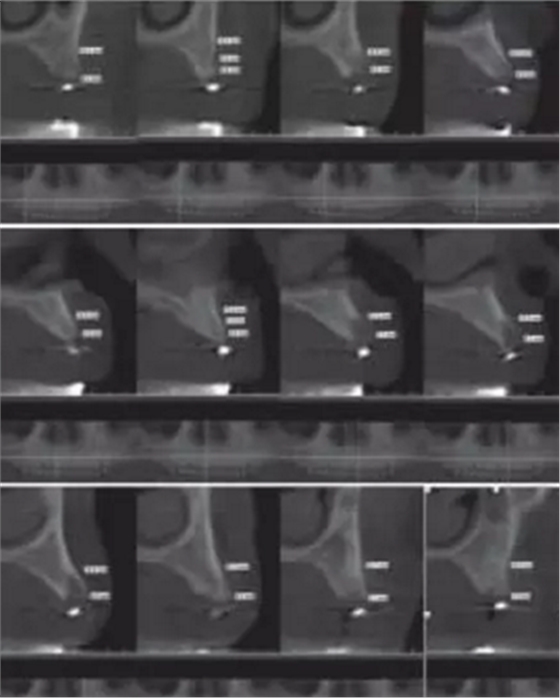

1.2.3治療過程:先行微創(chuàng)拔除14、13、21、22、23、24及25,搔刮拔牙窩去除炎癥組織,常規(guī)制作一副上頜過渡義齒(圖4,5)。2個月拔牙術后復診,利用上頜過渡義齒作為個性化托盤取上頜模型并翻制石膏模型,在石膏模型上根據過渡義齒標出各個牙位,同時利用壓膜機制作放射性模板(如圖6)?;颊吲宕鞣派湫阅0迮臄z全景片及CBCT(如圖7、8)。

圖8 佩戴放射性模板CBCT

放射性模板是指帶有放射性阻射標記物的模板,在患者種植手術前戴入口內并進行放射性拍攝,可評估種植位點骨質及可用骨量,從而設計種植體的數目、位點及方向,指導最終手術方案。放射性模板能顯示種植位點或未來修復體的信息,它的組織面需與其下方的粘膜緊密貼合且在放射性拍攝過程中保持穩(wěn)定位置。本病例首先按照全口修復計劃,給患者制作上頜過渡義齒。利用過渡義齒作為個性化托盤取模翻制石膏模型,并在石膏模型上按照過渡義齒標記牙位,繼而使用真空壓膜機制作樹脂薄膜導板,然后在樹脂導板相應牙位打孔并填塞放射性顯影的材料如牙膠。患者佩帶放射性模板進行錐形束CT(CBCT)的掃描,從而得到種植位點骨組織的情況。牙列缺失的患者其放射性模板由粘膜支持,有可能在放射性掃描的過程中移位,可使用咬合記錄進行固定。本病例所制作的放射性模板與患者的粘膜較為貼合,有較強的固位力。